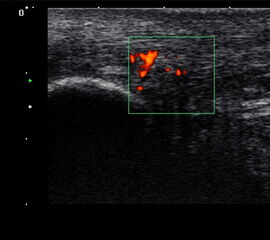

Die Farb-Doppler-Sonographie wurde 2001 erstmalig von Ohberg und Alfredson in Umea in Schweden bei schmerzhaften Achillessehnen eingesetzt 17. Bei 21 symptomatischen Sehnen konnten intratendionös mit Hilfe der Farb-Doppler-Sonographie pathologische Blutgefäße als Neovaskularisation nachgewiesen werden, die sich bei Achilles-gesunden Kontrollgruppe nicht fanden. Wenig später berichtete dieselbe Arbeitsgruppe über die erfolgreiche Farb-Doppler-kontrollierte Sklerosierung der Neogefäße mit Polidocanol 18.

2001 verglich Richards et al. die Power-Doppler-Sonographie bei symptomatischen Achillessehnenbeschwerden mit der Magnetresonanztomographie 19. Die Neogefäße in der Power-Doppler-Sonographie korrelierten mit Signalveränderungen in den T2-gewichteten MRT-Sequenzen. Aufgrund der guten Reproduzierbarkeit und Verfügbarkeit hat sich die Power-Doppler-Sonographie inzwischen bei der Darstellung der kleinen Neogefäße mit ihrem langsamen Blutfluss etabliert 202122. Die Neogefäße dringen von ventral in die Achillessehne ein. Typischerweise sind diese Neogefäße erst ab einem Sehnendurchmesser von >6,5mm nachweisbar. Bei erfolgreich behandelter Achillestendinopathie kann nach einem Jahr ein Rückgang der Anzahl der Neogefäße in der Power-Doppler-Sonographie, eine Durchmesserreduktion sowie eine Normalisierung der MRT-Signalalteration beobachtet werden 23. In einer Fallstudie konnte ein Abfall des Neovaskularisationsvolumens bei einem Patienten mit mid-portion Achillestendinopathie von 463mm3 auf 117mm3 belegt werden 24. Dies ging mit einer Verbesserung des Schmerzes in der visuellen Analogskala (von 8 auf 0) und des VISA-Scores (von 2 auf 92) einher.

634 asymptomatische Marathonläufer wurden mit der hochauflösenden Power-Doppler-Sonographie (12MHz) anlässlich von 23 Marathonveranstaltungen und 6 und 12 Monate im Anschluss untersucht 25. Mit einer odds ratio von 6.9 (p<0,001) konnte eine Neovaskularisation bei asymptomatischen Läufern die Entwicklung einer midportion Achillestendinopathie anzeigen. Eine positive Vorgeschichte für Achillessehnenbeschwerden hatte eine odds ratio von 3,8 und stellt damit ebenfalls einen ernst zu nehmenden Risikofaktor für weitere Beschwerden dar.

Power-Doppler-kontrollierte Sklerosierung mit Polidocanol

Die Farb-Doppler- oder auch Power-Doppler-gesteuerter extratendinöse Sklerosierung der Neogefäße und der begleitenden Schmerzfasern ist ein etabliertes Konzept zur Therapie der Achillestendinopathie. Ohberg und Alfredson stellten 2002 ihre Pilotergebnisse bei zehn Patienten mit mid-portion Achillestendinopathie vor 18. Die Schmerzstärke reduzierte sich signifikant von 74 auf 8 bei acht der zehn Respondern. Auch in einem randomisiert-kontrolliertem Studiendesign konnten die positiven Effekte der extratendinösen Sklerosierung mit Polidocanol bestätigt werden 48. Der Abstand zwischen zwei Sklerosierungen sollte mindestens 6 Wochen betragen 49. Der Sehnendurchmesser nimmt durch eine Sklerosierungstherapie von 10 auf 8mm signifikant ab im Sinne eines Remodellings der Achillessehne 50. Unterschiede zwischen einer Polidocanoldosierung von 5 und 10mg/ml konnten in einer randomisierten Studie nicht identifiziert werden 51. Auch bei Ansatztendinopathie kann die Sklerosierung im Bereich des Karger-Fettkörpers signifikant den Schmerz reduzieren 52. Eine Studie verglich die Polidocanolsklerosierung mit einer Farbdoppler-gestützten Chirurgie an der Achillessehne 53. Die klinische Schmerzreduktion war in beiden Studiengruppen gleich mit einer Infektion in der Operationsgruppe.